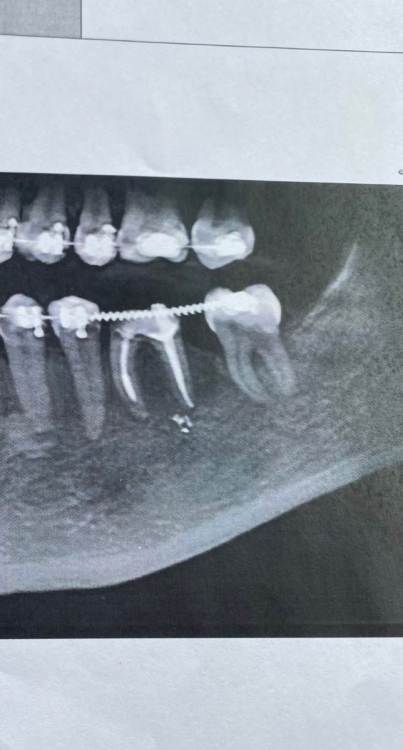

K3000 Опубликовано 24 марта, 2022 Поделиться Опубликовано 24 марта, 2022 Здравствуйте всем! Хотела узнать у специалистов какие варианты у меня есть с моим зубом. Это многострадальная нижняя 6ка, разрушена на уровне десны уже лет как 10, в зуб был поставлен штифт и был покрыт коронкой, но коронка слетела( простояв около 3х лет). 2 года ходила в брикетах и верхний зуб антагонист был немного поднят( чтоб освободить место) . Сейчас вопрос , что делать с 6ой , удалять и ставить имплант или пытаться перелечить зуб( сказали что корень хороший , но сильно разрушен зуб, надо вытаскивать штифт, что опасно и можно сломать корень зуба). Снимки зуба прилагаю. https://imgur.com/a/XaGq50M Ссылка на комментарий

Irouil Опубликовано 24 марта, 2022 Поделиться Опубликовано 24 марта, 2022 Условия для имплантации близки к оптимальным, условия для сохранения зуба близки к неподходящим Я бы исходил из мнения протезиста, в моей практике в 99% случаев такие зубы ортопеды отправляют на удаление 1 1 Ссылка на комментарий